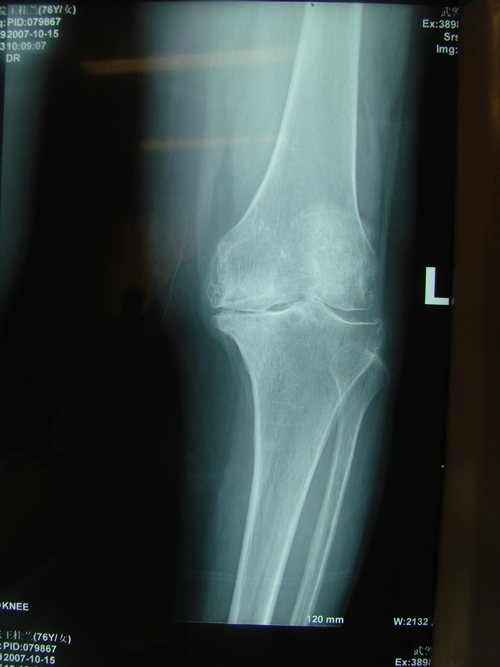

丁香园论坛>影像核医学>帖子详情>指由各种原因导致的局部关节软骨

图片尺寸2348x1796